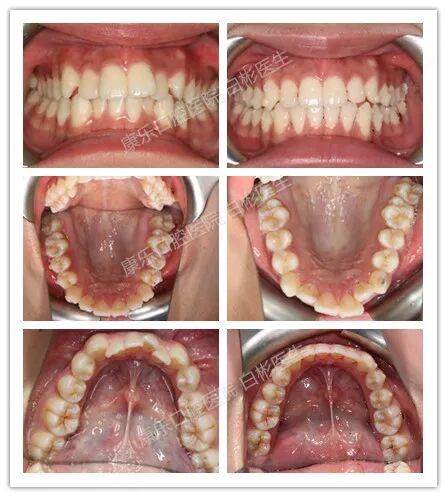

身处在这个看脸的时代 “变美”虽不是唯一解决办法 但没有好看的皮囊 谁会发现你有趣的灵魂呢? 可别因为牙齿不好看,让你不能开怀大笑 福 利 来 了 活动介绍 活动时间: 8月23日(周日)15:00--16:30 活动地点: 柳州康乐口腔医院总院(三中路25号) 活动内容: 1、签到入座; 2、白彬副院长正畸专题讲座; 3、案例分享及互动; 4、免费体验iTero口扫黑科技; 5.名额有限,预约从速喔!!! 到院好礼 ① 到场即送精美伴手礼一份 ② 价值1430元全系正畸精密检查0元享 (含口腔全景片75元、头颅侧位片75元、口腔CBCT380元、 取模+正畸方案设计费900元) ③ 免费体验价值680元iTero口扫 ④ 活动当天还可享受专属矫正活动价 报名方式 1、关注本平台,直接回复“微笑课堂+姓名+电话”即可,报名后请留意电话通知。 2、添加客服微信18577277737报名。 2、活动时间:2020年8月23日(周日)15:00 3、有任何疑问可以添加客服微信咨询哦。 扫码免费报名 主讲人 白彬 康乐口腔医院业务副院长 正畸中心主任 口腔正畸专科硕士 主治医师 美国隐适美隐形矫治认证医师 中华口腔医学会正畸专业委员会(COS)会员 隐适美(Invisalign)柳州地区特邀讲师 擅长方向| 隐形矫治技术,直丝弓矫治技术,对青少年、成人矫治复杂疑难病例有丰富经验,运用微种植钉技术矫形改善骨性上颌前突的核心技术为市级领先水准。 从业经验| 曾担任市三甲医院口腔科正畸主管职务,大型三级甲等医院十余年临床工作经验,累计成功矫治病例两千例以上,广西首批美国隐适美矫治认证医师。 美国隐适美培训讲师 康乐口腔作为柳州市最早开展隐形矫治的医疗机构,正畸团队平均每位医师都有1000+成功正畸案例的临床经验。 正畸中心白彬主任是广西柳州隐适美隐形矫治的培训特邀讲师,隐形矫治病例数在柳州地区名列前茅。 白彬医生与隐适美高级讲师刘鹤婷老师在2019年12月上海隐适美讲师会议合影 2019年4月29日,广西区隐适美新医师培训课程TC1首次在柳州市举办,白彬医生作为特邀讲师分享临床病例与经验。 主治案例| 牙列拥挤在使用隐形矫正1年内排齐,快速、安全、可靠,避免了美容牙套大范围磨除自己健康牙齿的苦恼。重新绽放美丽笑容,享受精彩美好的人生。 康乐口腔正畸团队 康乐口腔数字化美学正畸中心,专注于口腔正畸的临床医疗和研究。 ▲康乐口腔正畸团队拥有多位名校全日制正畸专科硕士 ▲正畸团队成员5~10年以上三甲医院就职经历 ▲正畸团队平均每位医师1500+正畸案例数 ▲正畸团队成员近20年口腔临床经验,师从名校名师。 对于正畸医生而言,除了帮助患者排齐牙齿,还要重塑牙齿咬合关系、以及让患者的面部变得更协调、美观。 为满足患者的美观要求,康乐口腔正畸团队在多年“美学正畸”的实践基础上,实现了以生物力学、颌面型为导向的正畸治疗,突破技术难点,做到数字化、个性化、精准稳定的方案定制,让矫治实现美观、健康、功能稳定的三大目标。 有这样一个东西 只要在嘴里轻轻一扫5分钟 你的矫正结果就会被“计算”出来 你可以清清楚楚地提前预知未来的自己 是不是很“黑科技”? 没错!这就是iTero口内扫描仪! 隐适美矫正新科技——iTero口腔扫描仪 1分钟扫描 3分钟成模型 5分钟预知矫正效果 代替传统取模 在口内进行电子扫描成像取模 iTero是什么 iTero口腔扫描仪 一台快速获取、传输口腔3D数据的仪器 它能代替传统的硅橡胶取模环节 让医生和客户对牙齿移动情况一目了然 几分钟则可立马预览矫正后的3D效果 iTero有哪些优势? 1 1 1 更舒适的矫正体验 传统取模 张口时间长、口内异物感强 iTero口腔扫描仪 减少张口时间、提高就诊舒适度 1 2 1 更快捷的取模过程 传统取模 整口取硅橡胶模型(约20分钟) 邮寄模型至美国隐适美公司(约15天) iTero口腔扫描仪 整口取模型(约5分钟) 将成像效果上传至隐适美后台(即时) 1 3 1 更快的预览矫正效果 传统取模 技师加工制作3D动画方案(约30天) iTero口腔扫描仪 即刻预览矫正后的效果(约5分钟) 1 4 1 更便捷的复诊监控功能 传统取模 无法直接监控复诊 iTero口腔扫描仪 随时调整矫治器佩戴进度 实行治疗进展评估 除舒适度、精确度高等优势之外 iTero更方便于 牙周病和咬合关系不稳的患者 别再观望了~ 矫正越早越好!